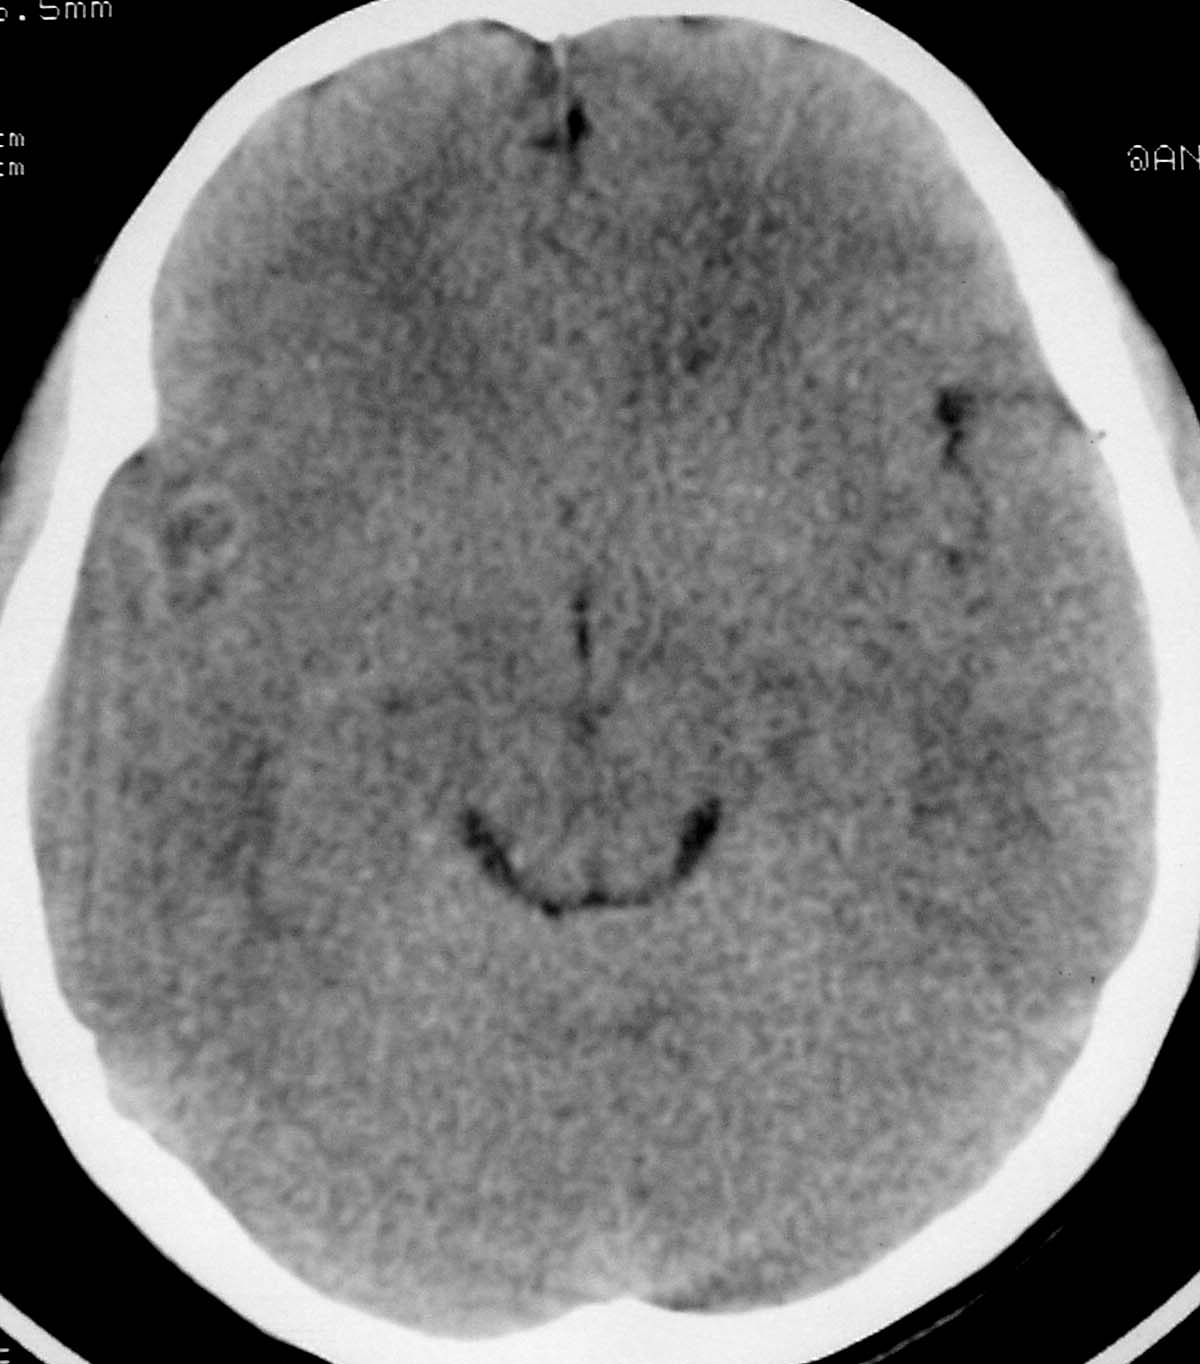

以下是引用余辉在2007-4-28 19:55:00的发言:[br]血管畸形?增强一下

以下是引用jw-830在2007-4-28 20:22:00的发言:[br]考虑血管畸形可能建议增强

以下是引用ysxyy在2007-4-29 21:14:00的发言:[br]像是假像,如果不放心可以偿试一下:[br]你用听眦线为基线扫一下,再用听眶线扫一下,就是说用不同的角度扫同一个地方;[br]看看有无变化,是不是有相同或相似的表现,即可鉴别;